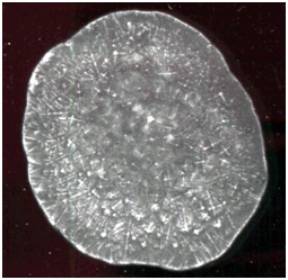

Результаты и обсуждения: Типичная

тезиографическая картина лизата лейкоцитов здоровых людей представлена на

рисунке 1.

Рис.1 Типичная

тезиографическая картина лизата лейкоцитов здоровых людей

Типичная

тезиограмма лизата лейкоцитов здоровых доноров характеризовалась следующими

особенностями: в центральной зоне расположены крестообразные кристаллы средних

размеров. Промежуточная зона представлена длинными кристаллами, расположенными

радиально, крестообразными кристаллами и мелкими неправильной формы. В краевой

зоне встречаются единичные длинные кристаллы [6].